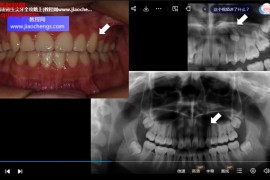

2021年张林口腔摄影视频课程18集数字化微笑设计电子书pdf完整版本百度网盘下载学习 张林 张林口腔摄影 张林数字化微笑设计 数字化微笑设计 数字化微笑设计pdf 数字化微笑设计下载 数字化微笑设计网盘